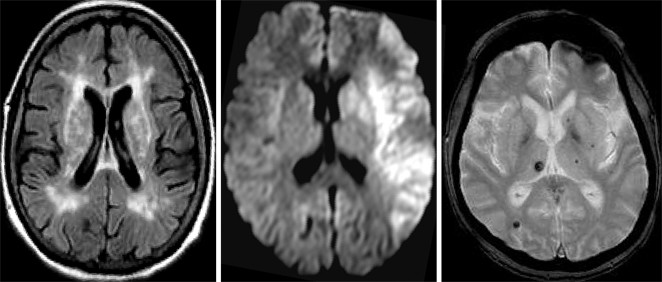

Figure 3 From Wert Der Konventionellen Mrt Flair Und T2 W Zur